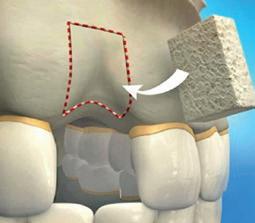

Кісткова тканина сполучна скелетна тканина, що складається з клітин-остеоцитів і міжклітинної речовини та формує кістки скелета. У міжклітинній речовині цієї тканини переважають неорганічні сполуки (приблизно 2/3 від загальної маси). Це вода й солі, здебільшого, фосфати й карбонати Кальцію, а також сполуки Флуору, Магнію, Натрію, що надають тканині твердості й щільності. Органічні речовини представлено переважно білком осеїном, який утворює волокна й забезпечує гнучкість та пружність кісток. На відміну від хрящової, у кістковій тканині є кровоносні судини необхідні для живлення клітин і росту кісток. Остеоцити мають відростки, за допомогою яких з’єднуються між собою для більшої міцності тканини та отримують поживні речовини з кровоносних судин. У кістках виокремлюють два види кісткової речовини — компактну й губчасту. Структурною одиницею компактної

Біологія + Стоматологія «Кісткова пластика є можливою завдяки тому, що кісткова тканина, на відміну від більшості інших тканин, має здатність до повної регенерації». Пояснюю твердження.